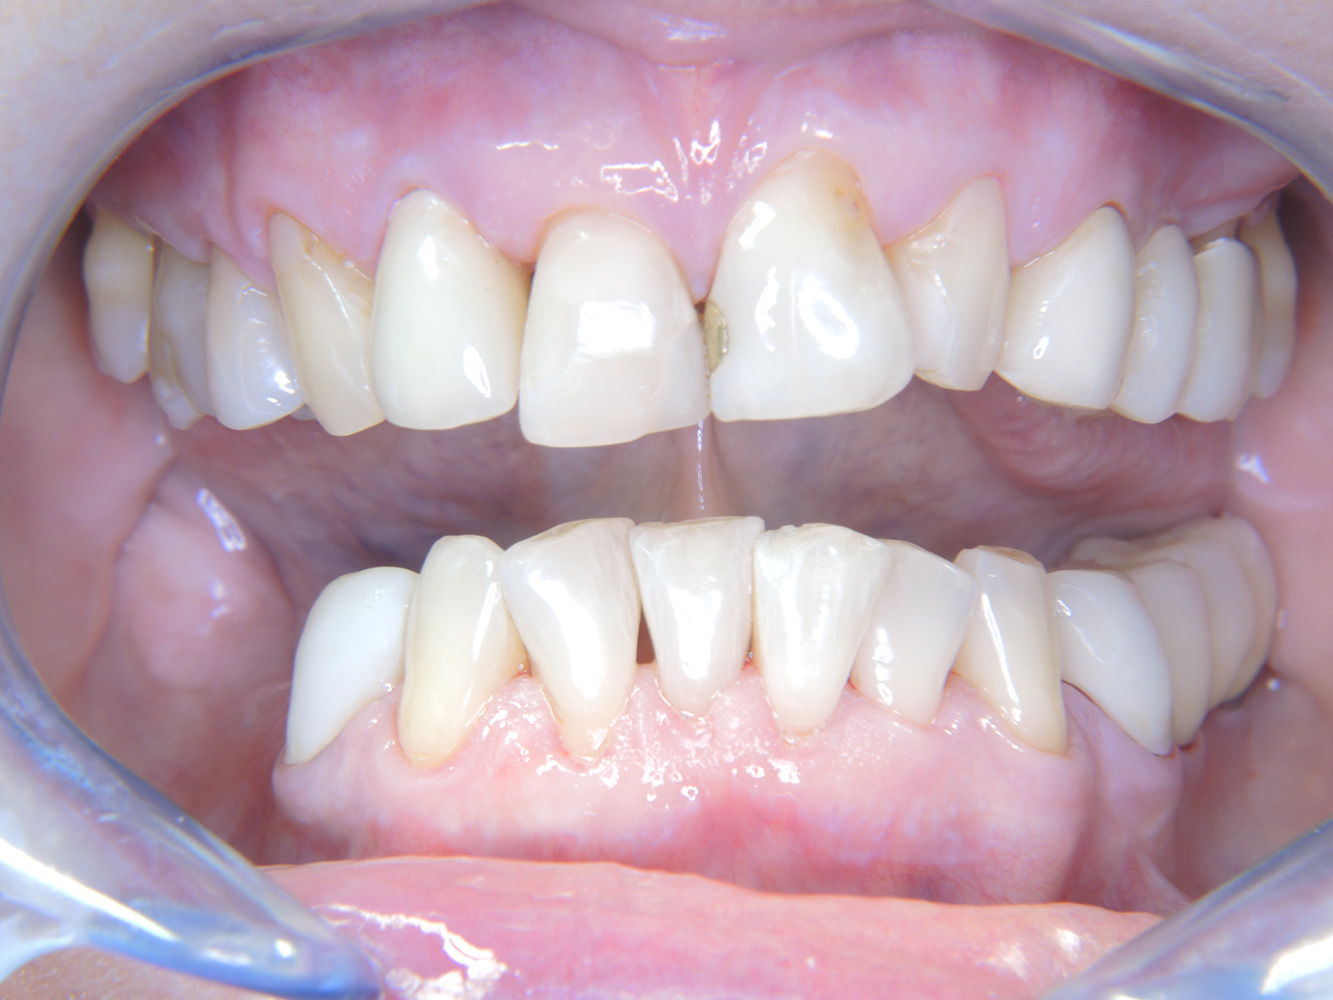

Siccome la paziente ha impianti e una malattia parodontale precedente, è a rischio di sviluppare una perimplantite. È pertanto consigliabile fissare

una seduta di richiamo ogni tre-quattro mesi.